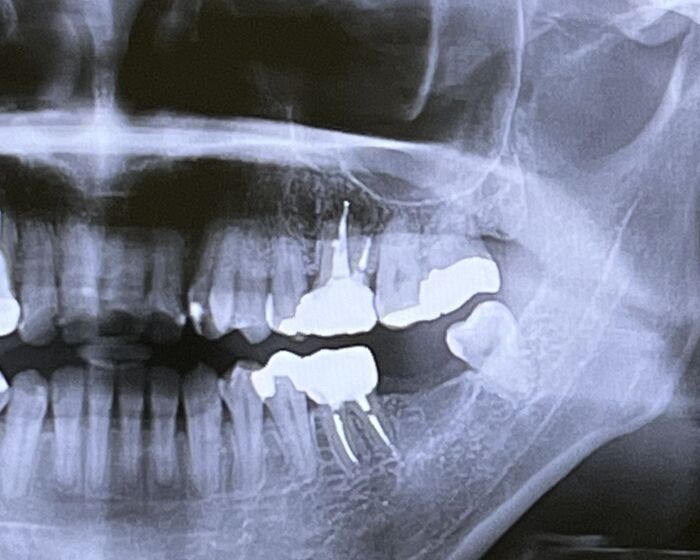

インプラント治療において、スキャンボディは非常に重要な役割を果たすツールです。インプラント治療は、歯を失った場所に人工の歯根を埋め込み、その上にクラウンやブリッジを取り付ける治療法です。この治療を高精度で行うために、スキャンボディは欠かせません。スキャンボディは、インプラントの埋入位置を精密に決めるために使用される特殊なツールです。スキャンボディは通常、インプラントの手術を行う前に、患者の口腔内の状態を詳細にスキャンする際に用いられます。これにより、インプラント治療の正確さと効果が大きく向上します。

スキャンボディは、患者の口腔内のスキャンデータをデジタル化し、そのデータを基にインプラントの位置や角度を正確に計算します。これにより、治療計画の精度が大幅に向上し、インプラントの埋入精度が確保されます。この精度向上により、治療後のトラブルや失敗のリスクを大きく減少させ、患者にとってより快適で安全な治療が実現します。さらに、スキャンボディは、インプラント治療を行う歯科医師にとっても非常に便利なツールです。デジタル化されたスキャンデータを基にしたシミュレーションによって、インプラントの最適な位置を選定できるため、治療の計画がスムーズに進みます。

スキャンボディは、インプラント治療において、3Dスキャンを活用し、非常に高い精度を提供する重要なツールです。インプラントの手術を行うためには、患者の口腔内の正確なデータが必要不可欠です。これを従来の方法で行うには、物理的な型取りが必要でしたが、スキャンボディを使用することで、デジタルスキャンによる精密なデータが取得できるようになりました。このデータは、そのままインプラント計画に反映され、精度の高い治療が行えるようになります。

スキャンボディの導入により、インプラント治療における様々な利点が生まれました。まず、患者への負担が軽減される点が挙げられます。物理的な型取りを行わず、3Dスキャンでデジタルデータを取得するため、患者の口腔内にかかる負担が大幅に減少します。さらに、スキャンボディは、インプラントの正確な位置を決定するだけでなく、角度や深さも含めた治療計画を支援します。これにより、従来の手法に比べて治療が迅速かつ効率的に進行し、患者の治療期間が短縮されることが期待できます。

また、スキャンボディは、インプラント治療におけるリスクを最小化するための鍵となります。従来の方法では、位置決めに誤差が生じる可能性があり、それが原因でインプラントが不適切に埋入されることがありました。しかし、スキャンボディを用いたデジタル計画では、その誤差が大幅に減少し、治療成功率を高めることができます。これにより、インプラントの失敗リスクを軽減し、より安定した治療結果を得ることが可能になります。